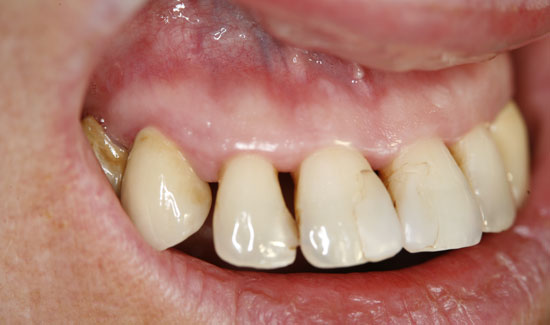

Die Patientin stellte sich in unserer Praxis vor mit der Frage der konservativen Erhaltbarkeit der Oberkieferfrontzähne bei chronischer Parodontitis. Wir fanden generalisierte Taschenbildungen (> 10 mm), Spontanblutungen und einen Lockerungsgrad 2/3, d.h. extraktionswürdige Zähne. Als Überbrückungsmaßnahme (Feiertagssituation) bis zu Sanierungsmaßnahmen boten wir ihr lokale Ozongasbehandlungen an.

Als Ozongasspender verwendeten wir Prozone, das mit Hilfe von Kunststoffansätzen Ozongas schmerzarm in die Taschen einzuleiten erlaubt. Die lokale Ozongas-applikation wurde dreimal im Wochenabstand wiederholt. Außerdem wurde die Patientin auf notwendige persönliche Hygienemaßnahmen aufmerksam gemacht. Wir konnten nicht nur die Blutungen stoppen, sondern den Lockerungs-grad der Zähne in einem stabilen Zustand (2) halten und die messbare Taschentiefe verringern.

Abb. 3: Zustand nach Ozontherapie. Chlorhexidinverfärbung der Zähne